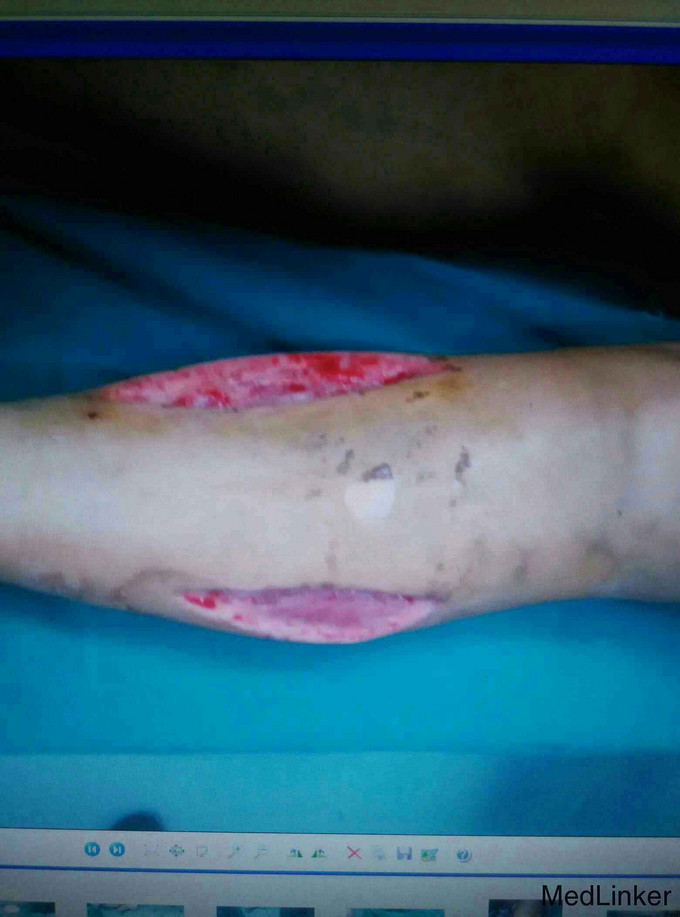

考虑为筋膜室综合征,予急诊行切开减压,考虑一期骨折复位内固定手术风险高,则行骨折端外固定架固定,同时VCD引流,待局部肿胀减轻,局部无明显张力,伤口无炎性反应后,二期行开放复位钢板固定术。

术后恢复良好,伤口正常愈合,功能佳。 讨论:小腿骨折常引起筋膜室综合征,应注意观察,特别是小腿上段骨折更容易引起筋膜室综合征,因为其血运好,出血多,如果发现筋膜室综合征或可疑筋膜室综合征,都要毫不犹豫的切开,不建议行一起的骨折端复位内固定,感染等风险较大,可暂时外固定架固定,同时VSD引流,可以减少换药及感染概率。术后7到10天局部肿胀减轻,无感染迹象后再行切开复位钢板固定术。